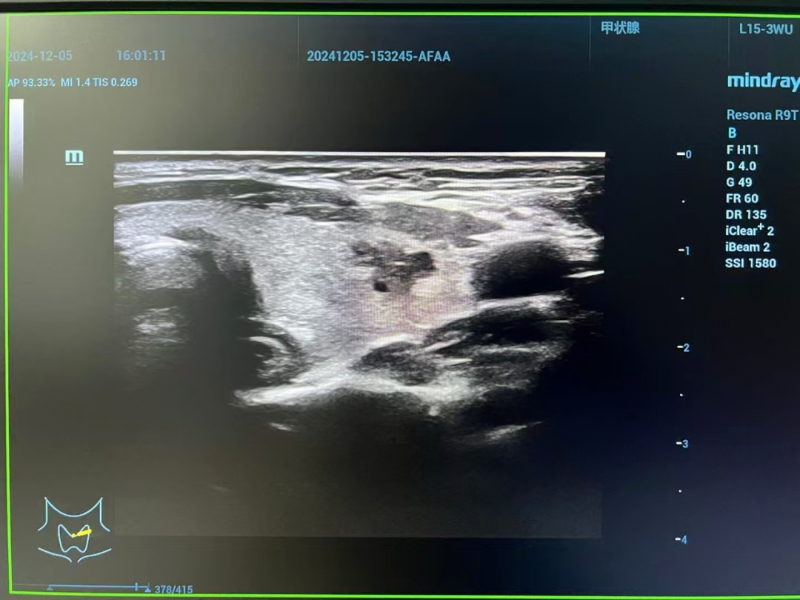

△术前评估

术前评估阶段,专家团队启用高分辨率颈部超声与先进磁共振成像技术,全方位、多维度扫描剖析。影像数据精准揭示:李女士左侧甲状腺结节小于1厘米,其包膜间距超2毫米,周边组织未现侵袭迹象,淋巴结转移亦无迹可寻。经严格筛选,甲状腺微小乳头状癌微波消融手术指征确凿无疑,为后续精准施治筑牢根基。